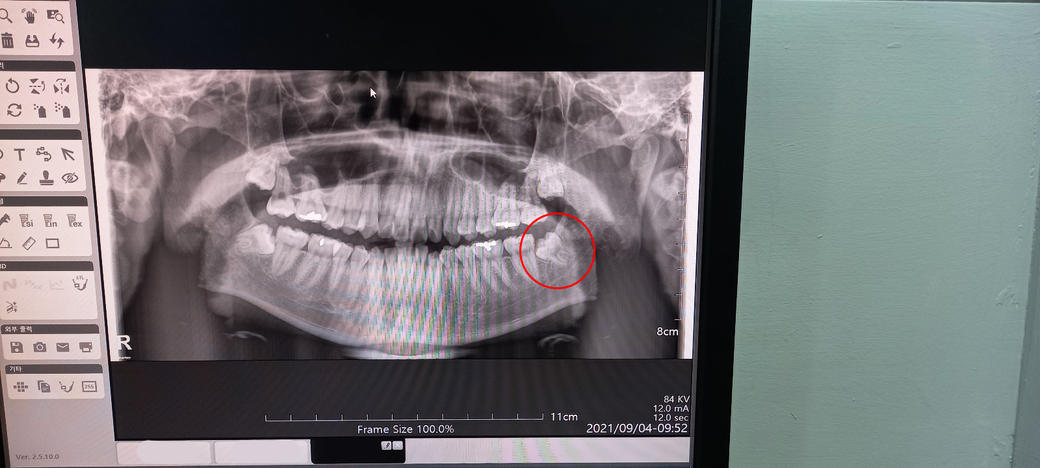

8월 22일 입대를 앞두고 갑작스레 왼쪽 아래 사랑니가 아픕니다.

바로 평소에 가던 치과에 가서 CT 찍어본 결과 당장 썩지는 않아 일단 소독하고 소염제와 진통제 등 처방받아 돌아왔습니다.

신경이랑 가까이 위치해서 조심해야한다고도 말씀하셨구요.

현재 왼쪽 아래 사랑니는 매복상태이고 그 옆 두번째 어금니에 영향을 줄 수도 있는 상황입니다.

멀쩡한 어금니의 뿌리를 흡수시킬 수도 있고 사이 충치를 만들 수도 있고 지금처럼 잇몸을 붓게 할수도 있습니다.(치관주위염)